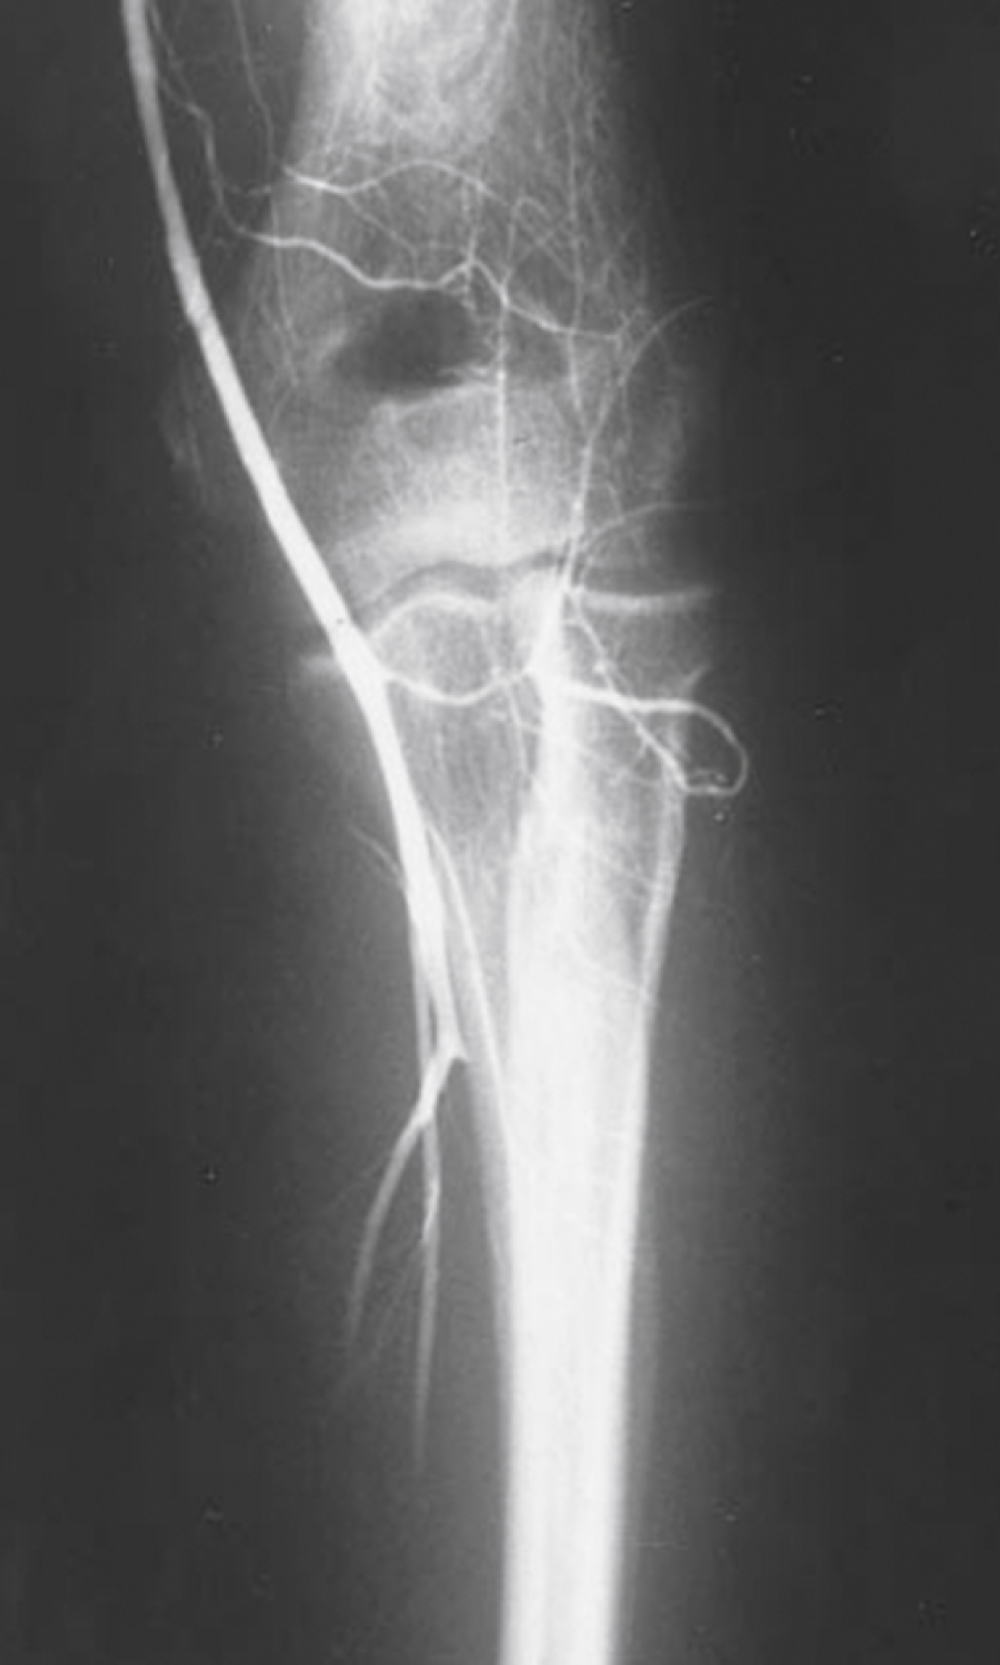

Intraluminal thrombosis ( Fig. 40.3 ) may occur in an injured artery acutely (within 24 hours) or may be delayed for many months. Acute thrombosis is initiated by stasis resulting from compression of the artery or from a disruption in the intima of an artery that becomes a nidus for thrombus formation. As the thrombus propagates, complete occlusion of the vessel can occur. Delayed thrombosis can occur months to years after injury if the injured vessel heals with stricture formation, resulting in decreased distal flow, followed by stasis and clot formation.

Complete thrombosis (arrow) of the distal brachial artery after reduction of a posterior elbow dislocation.

Courtesy D. Demetreades, MD.